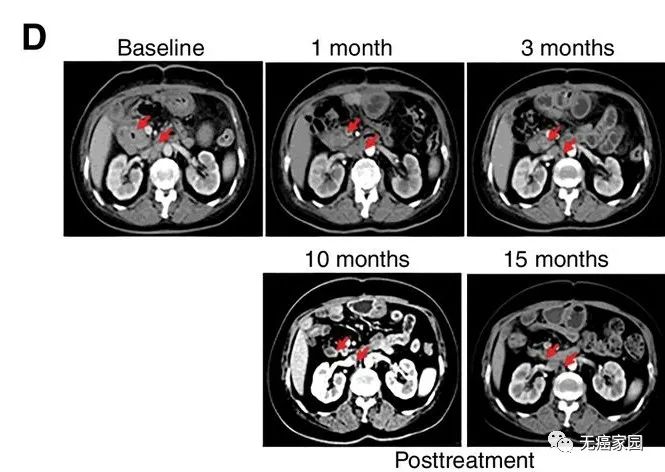

CART-RGFR细胞治疗之前和1、3、10和15个月患者1的CT扫描图像。

红色箭头表示原发肿瘤和腹膜后淋巴结转移。